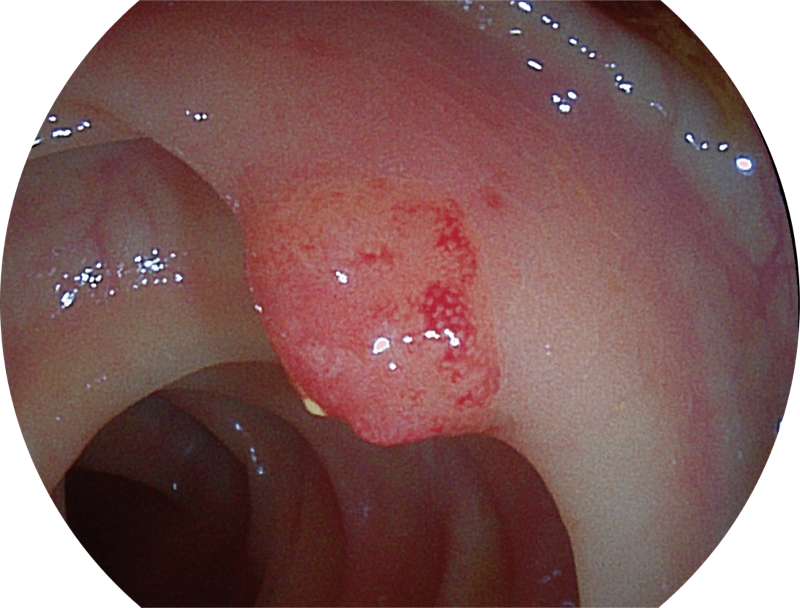

百万级像素高清传感器,1080P全高清视频信号输出,图像清晰。

白光图像